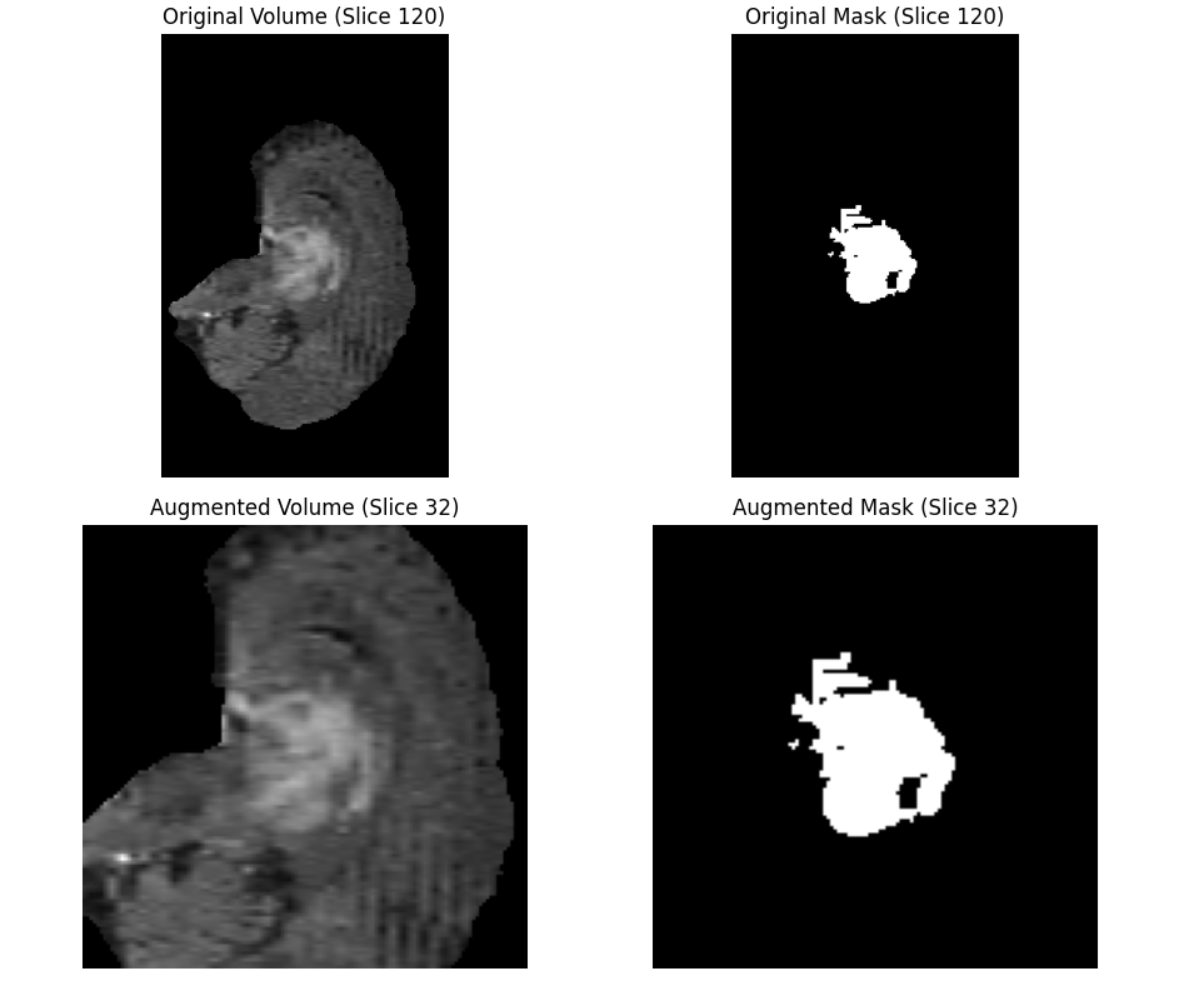

The following are the examples of 3D transforms in Albumentations.

CenterCrop3D: Crops a 3D volume (like a medical scan or video clip) from its center to a specified depth, height, and width. It extracts a central cube or cuboid from a 3D volume. This is similar to 2D center cropping but extended to 3D data with dimensions:

- Depth (number of slices or frames),

- Height (image rows),

- Width (image columns).

Key parameters used are:

size: Desired output crop size in (depth, height, width). Required.pad_if_needed: IfTrue, pads the volume with a constant value if it's smaller than the crop size.fill: Pixel value used to pad the image if padding is applied. Default:0.fill_mask: Value used to pad the mask if padding is needed. Default:0.p: Probability of applying the transform. Default:1.0.

The output is like following.

CoarseDropout3D: Randomly removes (sets to a constant value) several cuboid-shaped regions within a 3D volume (and optionally its mask). This simulates occlusion, sensor noise, or missing regions that are common in real-world 3D scans.

num_holes_range: Minimum and maximum number of cuboids to drop in each volume. Example:(2, 5)drops 2 to 5 cuboids randomly.hole_depth_range: Depth (z-dimension) of each dropout cuboid as a fraction of volume depth.hole_height_range: Height (y-dimension) of each dropout cuboid as a fraction of volume height.hole_width_range: Width (x-dimension) of each dropout cuboid as a fraction of volume width.fill: Value to fill dropped-out voxels. Can be a single number or a tuple for multi-channel data.fill_mask: Value to fill corresponding regions in the mask. If None, the mask stays untouched.p: Probability of applying this transform to a volume.

Following will be the output.

Pad3D: Add padding to 3D volumes, like medical scans, along the depth, height, and width dimensions. Padding adds extra voxels (3D pixels) on the sides of a volume and is often used to ensure a consistent shape across all samples or to prevent cropping of features during convolution.

padding: Specifies how much to pad each dimension.intpads all 6 sides (front/back, top/bottom, left/right) equally.tuple[int, int, int]pads symmetrically on all sides of each dimension (e.g. depth, height, width).tuple[int, int, int, int, int, int]allows different padding values for each side explicitly e.g. (depth_front, depth_back, height_top, height_bottom, width_left, width_right)fill(float or tuple): The value used to fill the padded voxels in the image volume. Default is 0.fill_mask(float or tuple): Fill value used for the mask (if provided). Default is0.p(float): Probability of applying the padding. Default is1.0(always apply).

Following is the output.

RandomCrop3D: Randomly crops a sub-volume of the specified (depth, height, width) from a 3D image. If the original volume is smaller than the crop size, it can optionally pad the volume before cropping.

size (tuple[int, int, int]): The output crop size specified as (depth, height, width).pad_if_needed(bool): Default isFalse, if set to True, the volume will be padded (using fill or fill_mask) when it's smaller than the requested crop size.fill(float or tuple): Default0, the value used to pad the image if needed.fill_mask(float or tuple): Default is0, the value used to pad the mask if needed.p(float): Default is1.0, the probability that this transform will be applied.

Output will be similar to following.